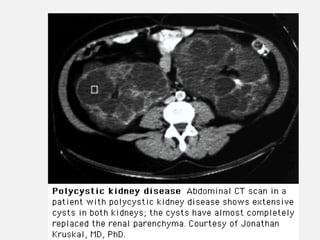

• DOENÇAS

• Rins policísticos.

PRINCIPAIS CAUSAS DEIRC • DOENÇAS SISTÊMICAS: • Diabetes mellitus. • H. arterial . • Doenças auto- imunes ( LES, Vasculites). • Amiloidose. • DOENÇAS HEREDITÁRIAS: • Rins policísticos. • Síndrome de Alport. • Cistinose.